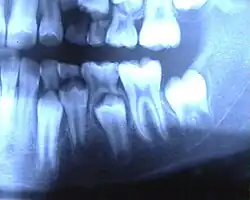

Die Milchzähne haben genauso wie die bleibenden Zähne Zahnwurzeln. Die Milchschneide- und Eckzähne haben eine Wurzel, die Milchmolaren haben im Unterkiefer zwei und im Oberkiefer drei Wurzeln. Anomalien sind im Milchgebiss sehr selten. Beim Zahnwechsel mit dem dadurch bedingten normalen Verlust der Milchzähne werden die Milchzahnwurzeln durch die nachdrängenden bleibenden Zähne resorbiert (aufgelöst); die Milchzähne scheinen keine Wurzeln (gehabt) zu haben.